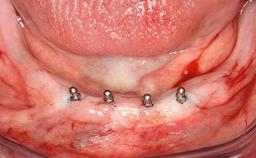

Oral Rehabilitation of an Elderly Edentulous Patient with Osteoarthritis Using an Implant-supported Mandibular Prosthesis with Locator Abutments

A 78-year-old man was referred to the dental hospital by his general dental practitioner. He was a non-smoker but was taking a number of medications as prescribed by his general medical practitioner, including atorvastatin-calcium for high cholesterol, lisinopril and hydrochlorothiazide for hypertension, warfarin as an anticoagulant, and metformin for the management of type 2 diabetes. The patient also suffered from osteoarthritis in both hands. The patient was edentulous in the maxilla and partially dentate in the mandible. A mandibular acrylic partial lower denture had been recently delivered but was poorly tolerated.

Defining Characteristics Fully edentulous lower jaw to be rehabilitated with two or more implants

Modality 2 interforaminal implants

Bone Volume Deficient horizontally, allowing simultaneous augumentation